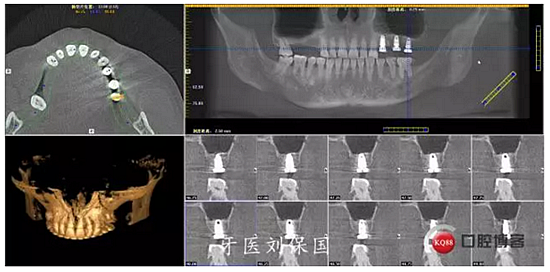

1.術(shù)前CT:

治療計劃及相關(guān)費用已向患者講明,征得患者同意,口腔及頜面部常規(guī)消毒,鋪巾,5.1ml必蘭局部浸潤麻醉下,切開,翻瓣,暴露牙槽骨,常規(guī)拔除患牙,清創(chuàng),沖洗,先鋒鉆定位,逐級擴孔,在25,26位置行上頜竇內(nèi)提術(shù),植入bio-oss骨粉,在24,25,26位置分別植入Dentium 4.5*8mm植體各一枚,扭矩30Ncm,旋入愈合基臺 603R,縫合,沖洗。

3.術(shù)后CT:

4.六個月后二期CT: